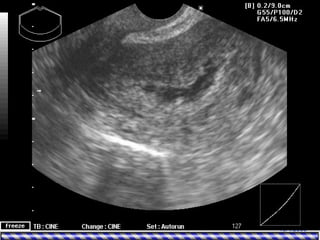

• Imaging

– TVS: it is a suitable screening test for

evaluation of the endometrial cavity.

• Timing: should be performed after menstruation in

the follicular phase of the menstrual cycle.

• Value:

– Sonohysterography is the sonographic

evaluation of the endometrial cavity following

the transcervical instillation of saline, an

approach that has comparable results for

structural anomalies of the endometrial cavity to

those of hysteroscopy.

– Radiographic hysterography is less accurate

than hysteroscopy for cavity evaluation.